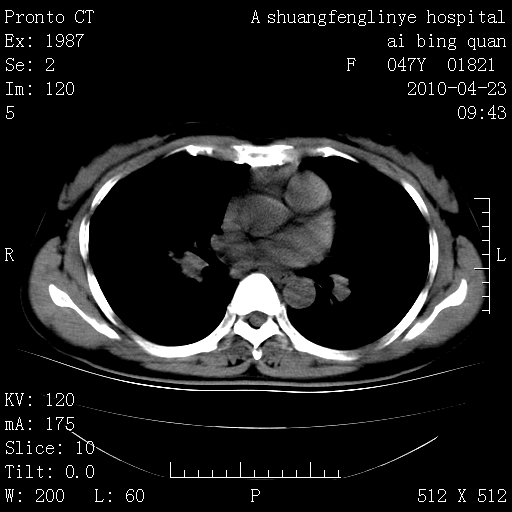

标题: CT25944:胸痛、气短、前几日高烧!肺Ca?请会诊! [打印本页]

标题: CT25944:胸痛、气短、前几日高烧!肺Ca?请会诊!

kaolv 周围型肺癌并同肺转移

双肺多发结节,考虑转移瘤,肺癌肺转移不除外

周围型肺癌并肺转移

双肺多发结节,部分密度较高,最大结节边缘光滑。临床有“胸痛、气短、前几日高烧”病史。首选考虑:右肺感染性病变!建议积极消炎后复查!